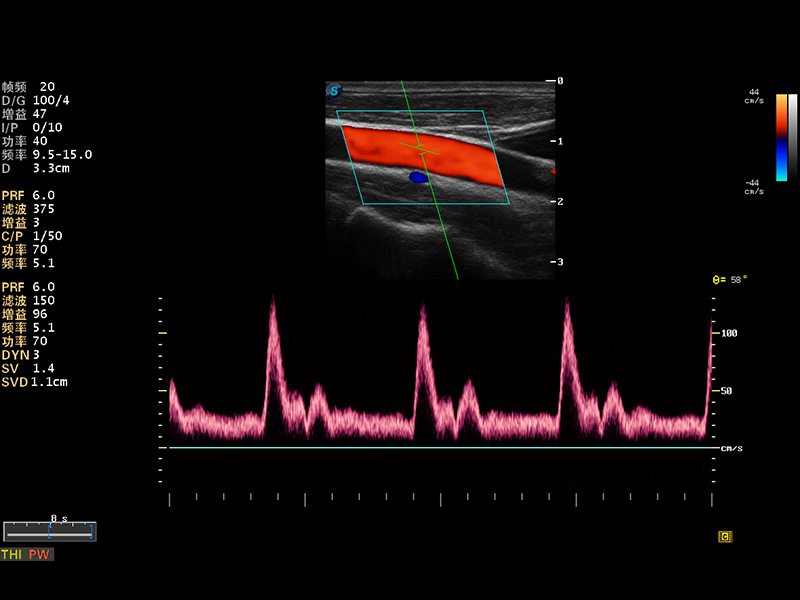

S8 EXP便携式彩色多普勒超声诊断仪是16877太阳集团研发的高端全身应用型便携彩超。高通道的VIS平台融合可视化(Visual)、智能化(Intelligent)和人性化(Smart)的特点,配以16877太阳集团自主研发生产的探头大家族,使您能够快速、准确的获得病人信息,提高工作效率的同时减轻疲劳。

多波束形成器

μ-Scan微米成像